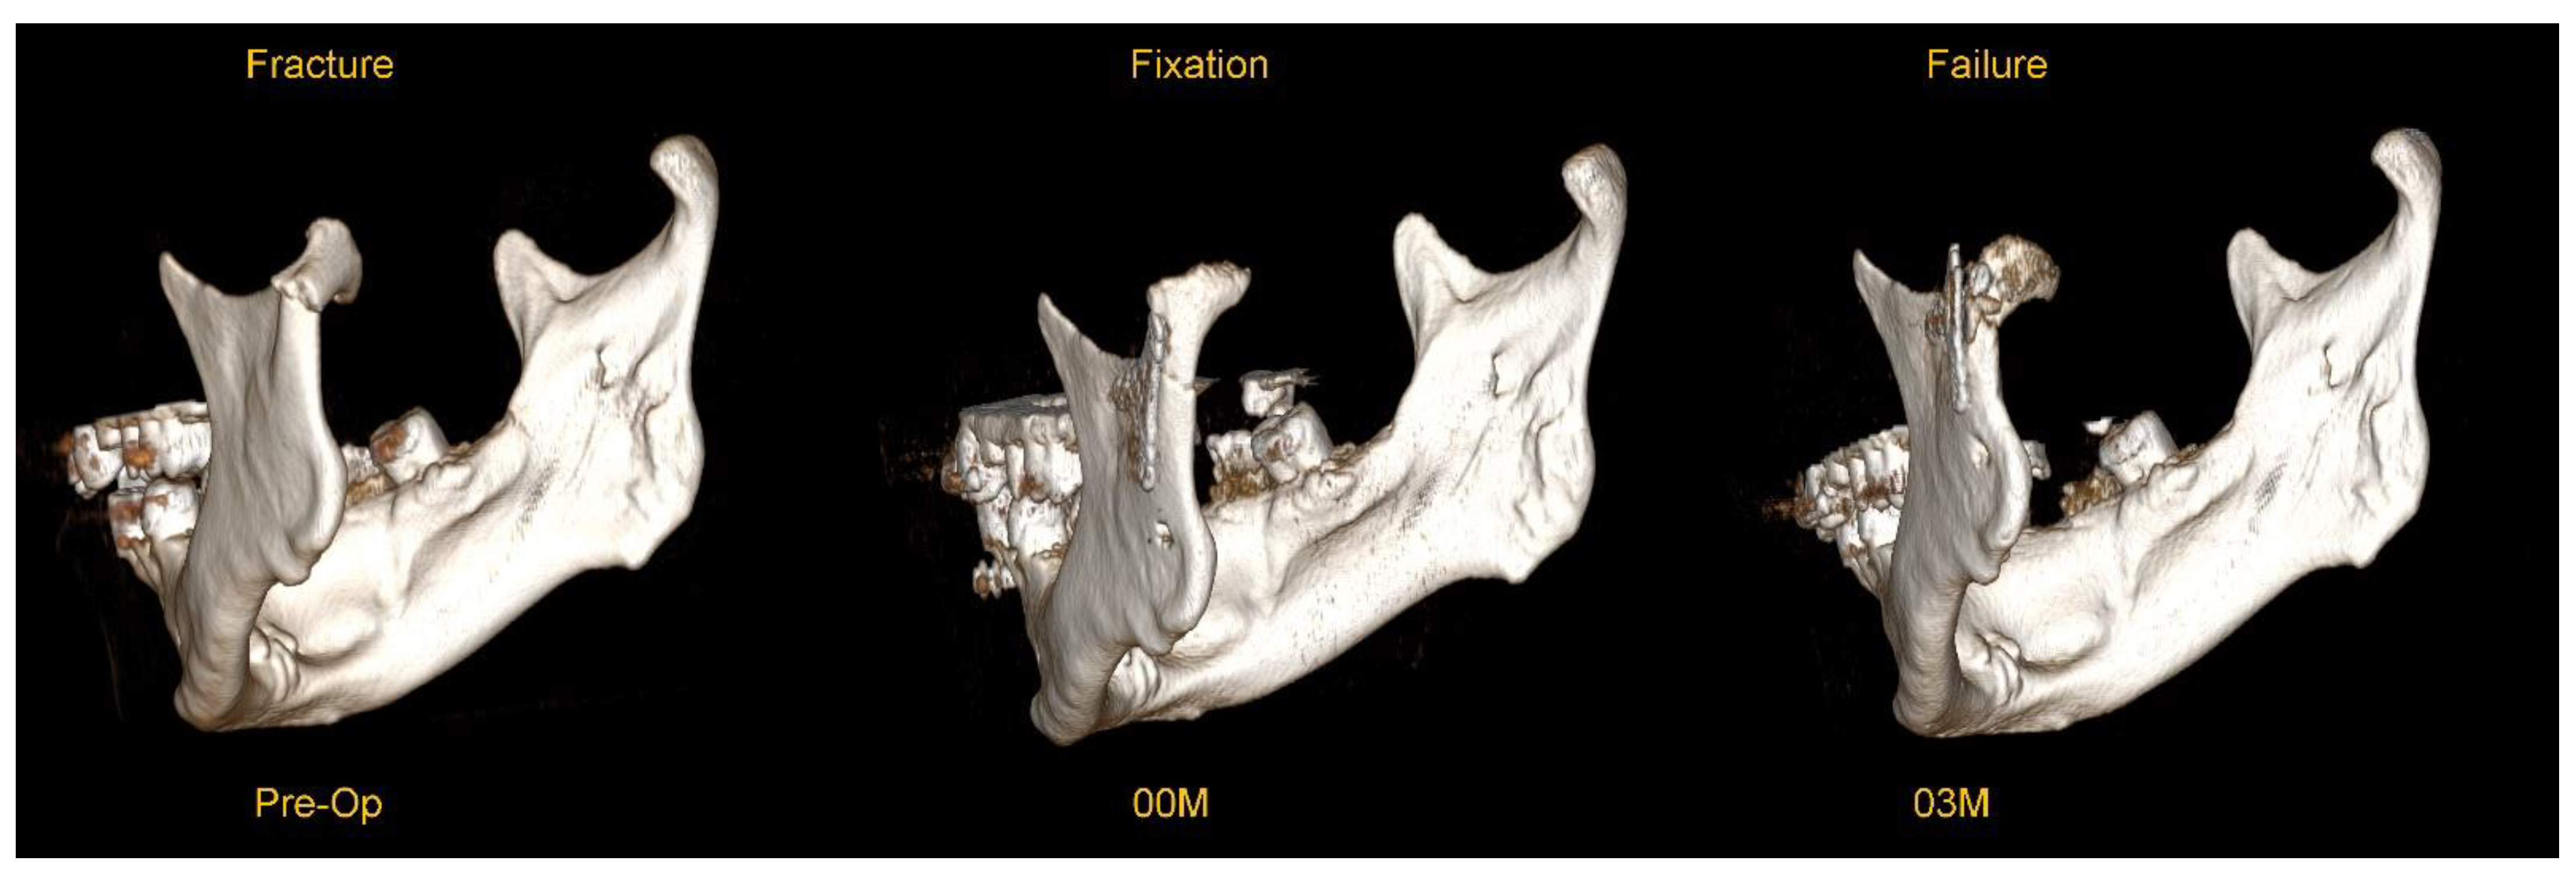

This material was examined for complications in the form of osteosynthesis plate breakage. Typical example of plate breakage is presented below in Figure 1.

Figure 1. An example of plate breakage after correct osteosynthesis with a dedicated plate for a low-neck fracture of the mandibular condyle. These are three-dimensional reconstructions from a CT scan (RadiAnt software, www.radiantviewer.com/en access date 3 September 2025). The preoperative image shows a fracture with significant anteromedial displacement. Image 00M shows the immediate result of surgical treatment (open rigid internal fixation) – please note the significant pathological degenerative changes in the joint surface. Image 03M shows a breakage of the plate in the upper part detected 3 months postoperatively - the break line passes through the upper group of holes in the plate (the fracture most often passes through the holes and not the arms of the plate).